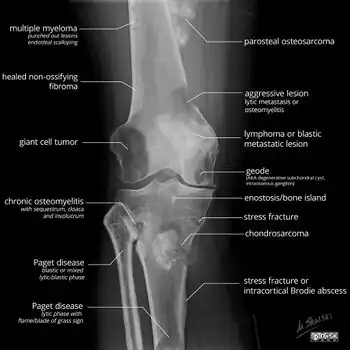

A bone tumor may be felt on examination, following which a plain X-ray is usually carried out.[4][13] Imaging is interpreted with the location of the lesion and the person's age being taken into account.[14]

X-ray appearances of different types of bone tumors in > 30 years. -